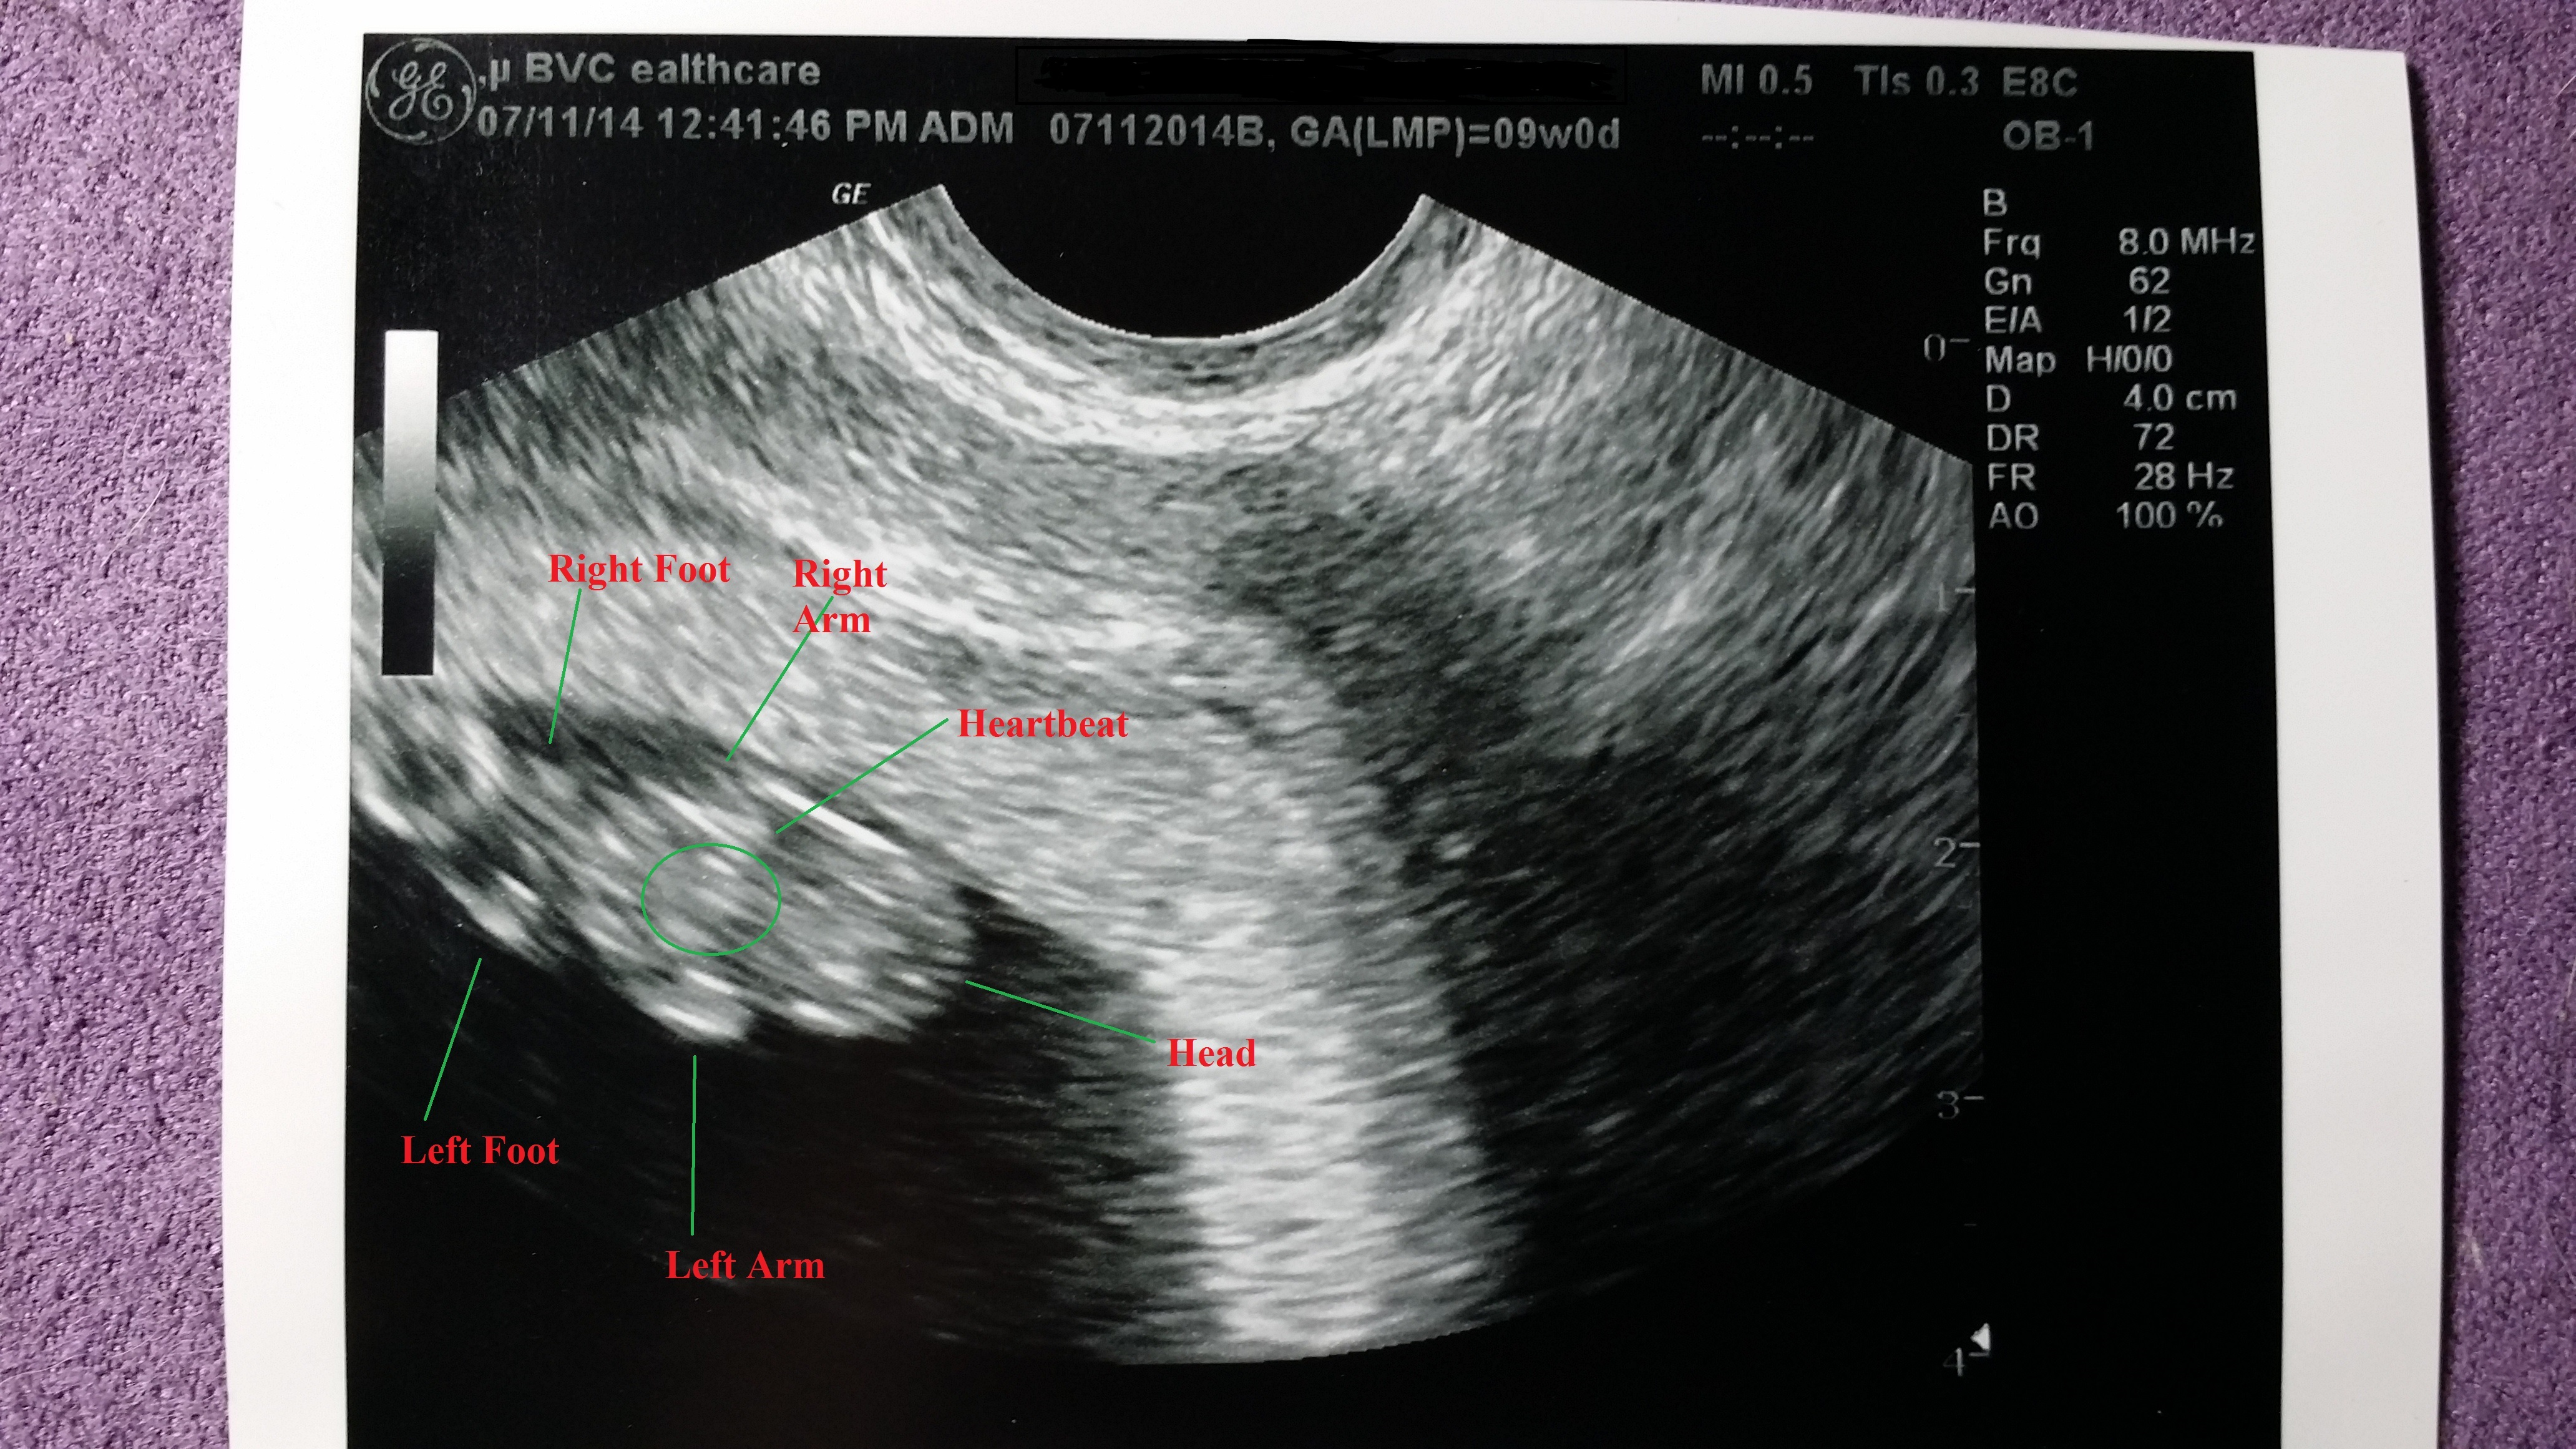

We had our first ultrasound this morning! Baby is healthy, measuring at just under 2cm, 8 weeks and 4 days, so not too far off from my 9 weeks mark! We have a strong heartbeat, unfortunately, we didn't get to hear it today. However, we saw the baby move during the ultrasound! It was absolutely amazing!

• How awesome that they labeled everything!!!